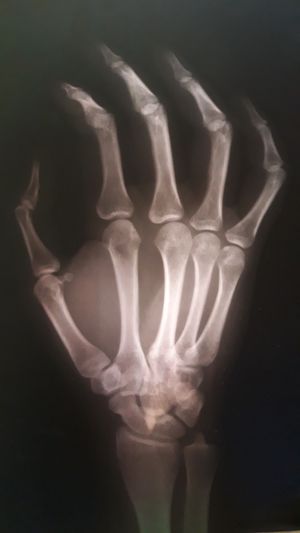

Is something happened to this hand??

My doctor said that i got a little dislocation in my tumb